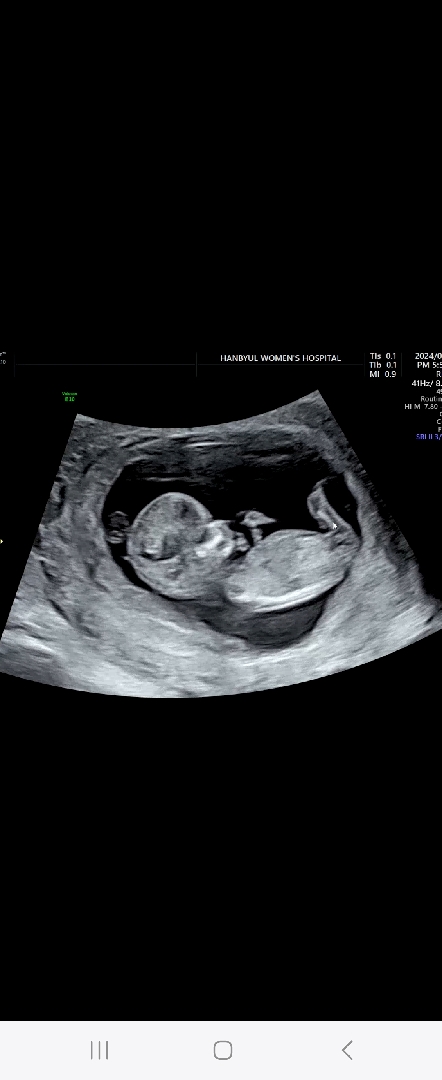

11주6일이에용~ 오늘 촘파보고왔는데 각도법 잘 보시는 맘들 봐주세용 ㅎㅎㅎ

네~~배촘파에용 아들인지.딸인지는용 ?? ㅠㅠ

오밀조밀해보여서 딸 처럼 느껴지긴하네요 ㅋㅋ 근데 각도법이 엉덩이 아래에서 위로보는 방향이 좀 정확도가 높다고해요

이사진에선 안보여요